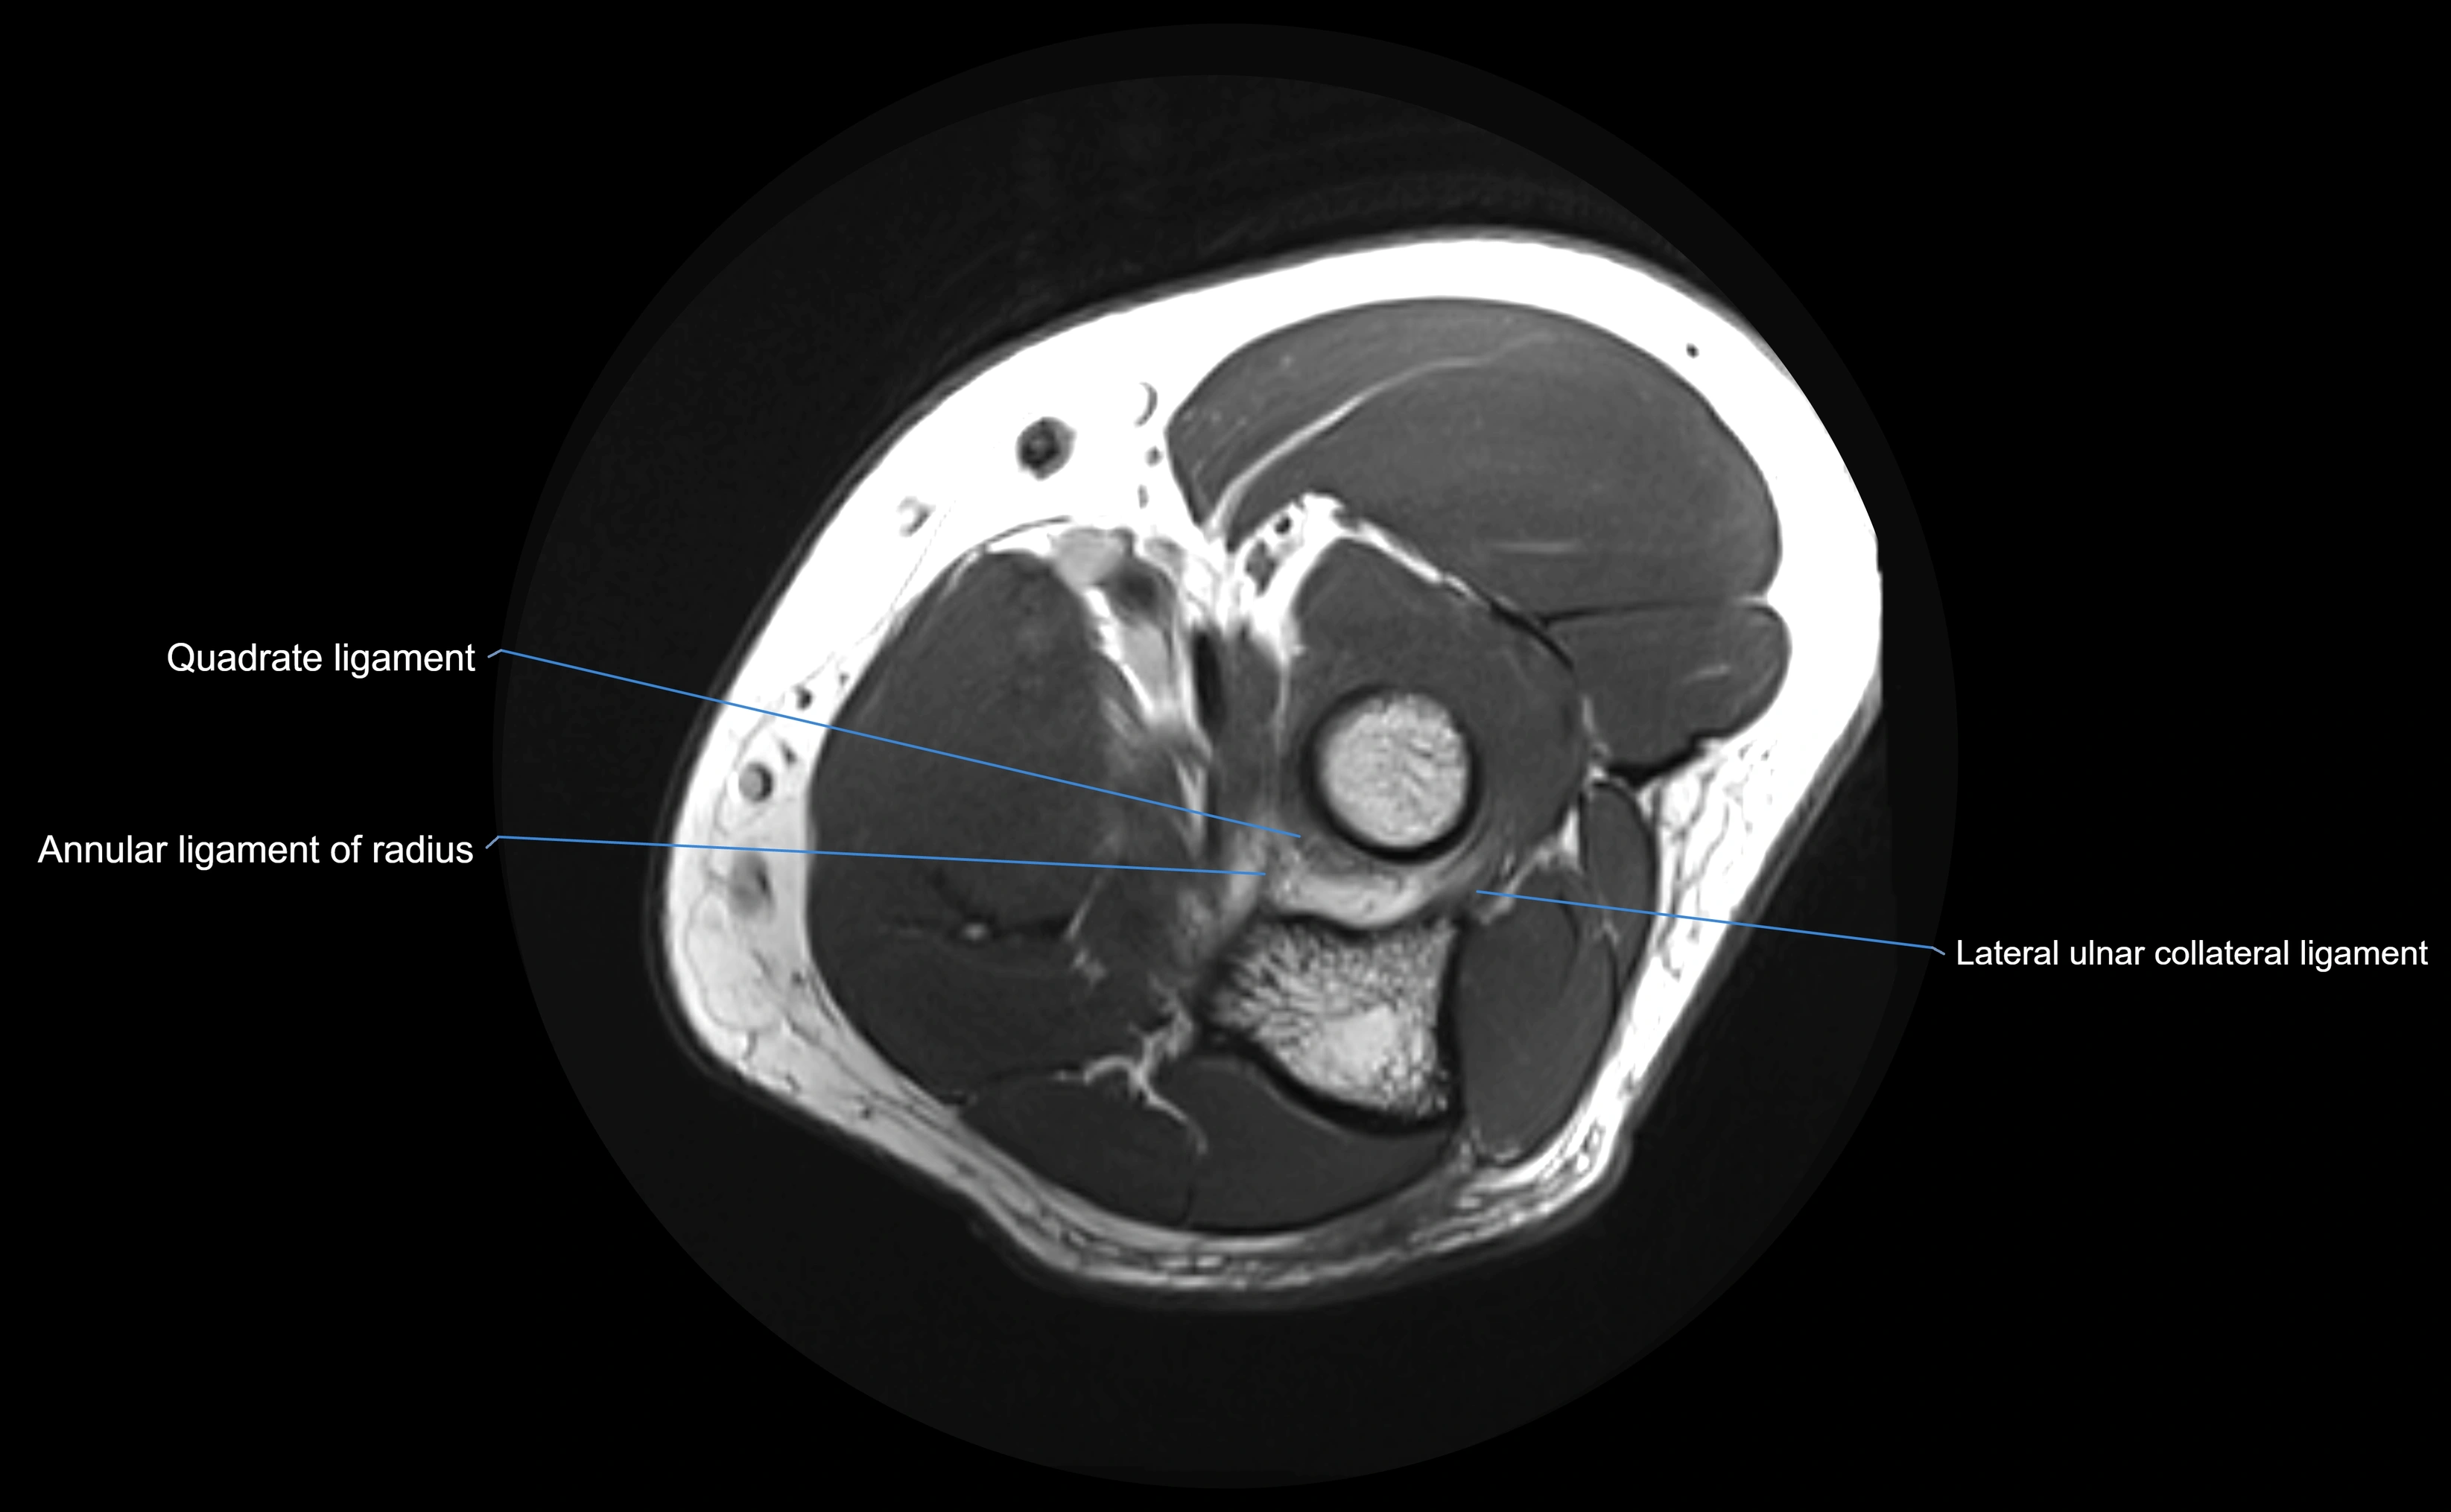

MRI Appearance

T1-weighted images:

• Ligament: low signal intensity (dark), appearing as a continuous band around the radial head.

• Adjacent fat and marrow: bright, creating contrast with the ligament.

• Thickening or disruption indicates injury or fibrosis.

• Joint capsule and synovium seen as thin low-signal lines contiguous with ligament margins.

T2-weighted images:

• Ligament: low signal (dark) with clear delineation from joint fluid.

• Fluid or edema: bright hyperintense, separating or surrounding the ligament in partial tears.

• Complete tear: discontinuity or non-visualization of ligament fibers, often with joint effusion.

Proton Density Fat-Saturated (PD FS):

• Normal: dark, well-defined band outlining the radial head.

• Partial tear: irregular or bright hyperintense signal within or adjacent to ligament fibers.

• Joint effusion and reactive synovitis appear bright and are well visualized.

MRI images

image